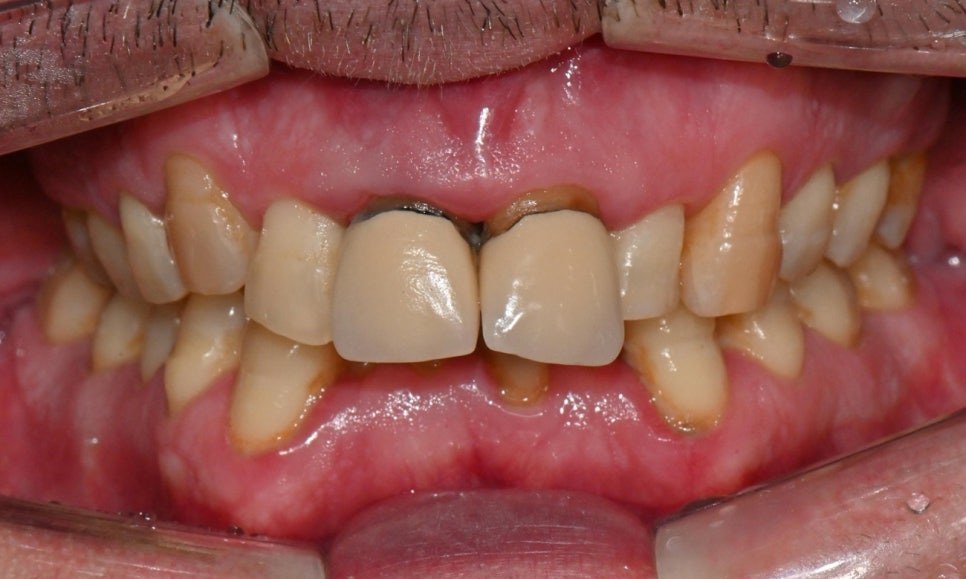

이 환자분은 영국에서 오신 40대 초반 남성분으로, 선천적으로 턱이 작아 어린 시절 턱을 앞으로 이동시키는 악교정 수술과 함께 약 6년 간 치아 교정을 받으셨다고 하셨습니다. 그러나 교정 치료가 충분히 만족스럽게 이루어지지 않았고, 이후 사고로 앞니를 다쳐 보철 치료를 받게 되었습니다. 시간이 지나면서 잇몸이 퇴축되어 앞니 보철물의 금속 부분이 노출되었으며, 제 2급 부정교합 및 불규칙한 치아 배열로 인해 심미적으로 정돈되지 못한 상태로 오랜 기간 지내오셨습니다. 이제는 앞니를 보다 아름답게 개선하고 싶다는 바람으로, 멀리 영국에서 한국까지 내원해 주셨습니다.

진단 결과, 교합시 하악 전치가 거의 보이지 않을 정도로 깊은 교합을 보이고 있었으며, 어린 시절 외상을 입었던 앞니는 치아 뿌리 부근에 광범위한 염증이 관찰되어 장기적인 유지가 어려운 상태였습니다. 이에 앞니 두 개는 발치를 결정하였고, 환자의 비교적 젊은 나이를 고려하여 가능한 한 최대한 치아를 보존하기 위해 앞니 부위 임플란트를 고려했습니다. 그러나 해당 부위 골 손실이 매우 심했고, 외국인 환자로 장기간 내원이 어려운 상황이었기 때문에, 광범위한 골이식을 동반한 임플란트 치료 보다는 비교적 짧은 기간 내에 기능과 심미를 회복할 수 있는 브릿지 보철 치료를 계획하였습니다.

2026-1-7 최종 보철물 장착 : 연세정원치과

치료가 모두 마무리된 후, 환자분의 미소는 이전과 비교해 전반적으로 한층 더 안정적이고 조화로운 인상으로 개선되었습니다. 앞니의 길이, 형태, 배열이 아랫입술 곡선을 따라 형성되는 smile arc와 자연스럽게 조화를 이루면서, 웃을 때 과도한 긴장감 없이 부드러운 심미적 균형을 회복할 수 있었습니다. 기능적인 교합 안정성과 함께 심미적인 만족도 역시 높게 나타났으며, 환자분도 결과에 대해 매우 만족해하셨습니다.